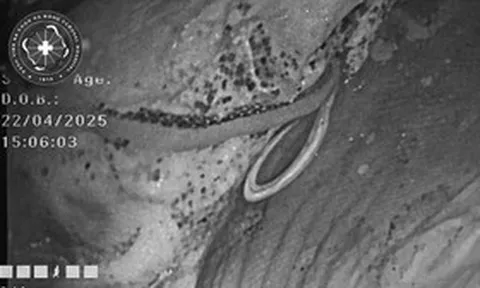

Ê-kip thực hiện ca phẫu thuật.

Ngay sau đó, gần 200 cán bộ y tế từ nhiều chuyên khoa lâm sàng và cận lâm sàng đã làm việc xuyên đêm với tinh thần khẩn trương và độ chính xác tuyệt đối.